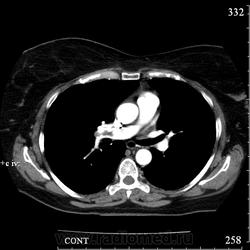

Коллега Mitkamfer спрашивал: "Может из наших коллег еще кто свои наблюдения покажет". Представляю случай ТЭЛА у женщины 57 лет с тромбозом подвздошной вены и распространением тромба в нижнюю полую вену.

Клиники особой не было, исследование делали с целью, а нет ли у нее еще и ТЭЛА. При КТ-ангиографии признаки пристеночных тромбов в правой и левой легочной артериях и единичных мелких пристеночных тромбов в мелких ветвях нижнедолевых артерий с обеих сторон, организовавшихся (лентовидных) тромбов в левой легочной артерии. При этом диаметры легочного ствола, правой и левой ЛА не расширены. Как видите, они такие разные, эти ТЭЛА

Изменения в легких при этом весьма скромные: в правом легком особых изменений нет, в левом - признаки организовавшегося инфаркта легкого - радиальные фиброзные тяжи в базально-латеральном сегменте нижней доли левого легкого.

Рисунок 32. Дополнительные КТ-ангиографические признаки ТЭЛА у больной 58 лет.